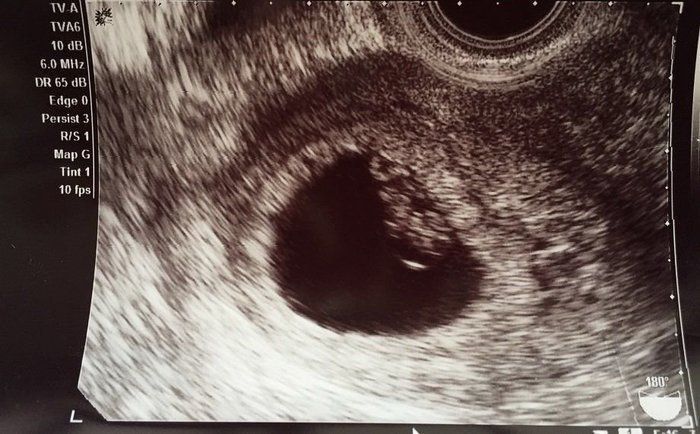

水野谷つむぎさんの妊娠6週目のエコー写真 心音が確認できた!

心音確認ができました。卵大の子宮の中にいて、1cmにも満たない大きさだと教えてもらいました。